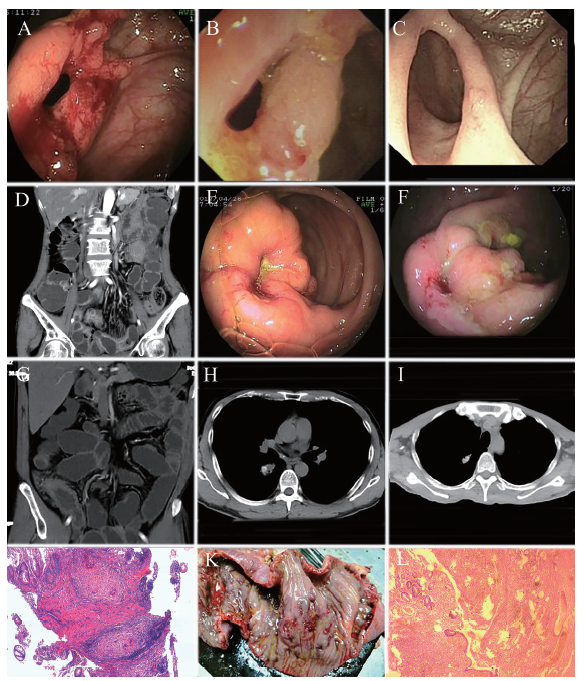

例1 患者女,50岁。因反复腹痛、大便不规律伴体质量下降半年于2014年7月18日入我院。患者既往身体健康,否认有“结核、伤寒”等慢性传染病史。入院体格检查:消瘦面容,心、肺听诊无异常,腹平、软,右下腹轻压痛,无反跳痛及肌紧张,墨菲征阴性,肝脾肋下未扪及,腹水征阴性,肠鸣音活跃。血常规、尿常规、粪便常规、肾功能、电解质、血糖、心肌酶谱、糖类抗原199、癌胚抗原、甲胎蛋白、CRP、心电图、腹部X线立位片均未见异常;结核抗体、梅毒抗体、HIV抗体均阴性。ESR 50 mm/h。肝功能示总蛋白52.9 g/L、白蛋白32.1g/L。HBsAg、抗-HBe、抗-HBc均为阳性,HBV定量2.0×103 IU/ml,结核感染T细胞(TB-IGRA)检测(+)、T-N的值为27.9 pg/ml。胸部CT示右上肺钙化灶。胃镜示非萎缩性胃窦炎。全腹部增强CT示肝右叶血管瘤、肠系膜多发淋巴结肿大。肠镜见末端回肠黏膜充血,一处纵行溃疡形成,回盲瓣口固定狭窄、环形溃疡形成,易出血,余升结肠、横结肠、降结肠、乙状结肠、直肠无异常。(回盲部)黏膜病理活组织检查(活检)示浅表黏膜慢性活动性炎症。全消化道钡餐示回盲瓣口细、窄,回肠末端见不规则充盈缺损。拟诊为“回盲部及回肠末端溃疡待查:结核可能性大、不排除克罗恩病,肝血管瘤,乙肝病毒携带”,予以异烟肼+利福平+乙胺丁醇三联诊断性抗结核治疗、双歧三联活菌调节菌群等处理,症状好转出院。出院后坚持服用抗结核药物治疗,3个月后复查肠镜示回盲部溃疡(好转)。继续服药12个月,复查肠镜示回盲瓣及回肠末端溃疡,病理活检示黏膜慢性炎症,于2016年1月18日第2次入院,血常规示血红蛋白104 g/L、红细胞4.02×1012/L、血小板184×109/L。尿常规、粪便常规、肾功能、电解质、血糖、ESR、凝血功能、心电图均无异常。肝功能示总蛋白58.3 g/L、白蛋白32.3 g/L。结核抗体阴性,CRP 5.29 mg/dl。胸部CT示右肺钙化灶。全消化道钡餐示空肠黏膜正常,回肠呈节段性狭窄及龛影,系膜缘纤维化,回肠末端见一类圆形充盈缺损,肠系膜区多发淋巴结肿大。全腹部CT及CT小肠成像示肝血管瘤,回肠节段性扩张、狭窄,肠系膜区多发淋巴结肿大,木梳征明显。最后诊断为克罗恩病(回结肠型、狭窄型、活动期,中度)、肝血管瘤。给予美沙拉嗪3 g/d、泼尼松40 mg/d抗炎以及复方嗜酸乳杆菌调节菌群等处理,于2016年5月查肠镜示回盲瓣溃疡(基本愈合),给予硫唑嘌呤100 mg/d维持治疗,期间未见腹痛、腹泻。患者因再次出现腹痛、腹泻于2017年3月21日第3次入院,查血常规示血红蛋白102 g/L、白细胞3.42×109/L、血小板252×109/L。尿常规、粪便常规、肾功能、电解质、血糖、补体C3、补体C4、凝血功能+D-二聚体、HIV抗体均无异常。CRP 4.78 mg/dl,ESR 32 mm/h。肝功能示总蛋白53.2 g/L、白蛋白29.5 g/L。胸部CT示右肺钙化灶。全消化道钡餐示空肠黏膜正常,回肠呈节段性狭窄及龛影,系膜缘纤维化,回肠末端见一类圆形充盈缺损,钡剂达回盲部。肠镜示回盲瓣及回肠末端溃疡(克罗恩病,活动期),给予泼尼松40 mg/d抗炎免疫调节、硫唑嘌呤100 mg/d调节免疫功能、肠内营养粉剂(安素)肠内营养等处理,3个月后复查肠镜提示回盲瓣溃疡(克罗恩病,基本治愈),继续服用硫唑嘌呤100 mg/d维持治疗1年,期间未见腹痛、腹泻,复查血常规、血液生化及CRP均正常,体质量增加5 kg。于2018年再次查肠镜示回盲瓣及回肠末端溃疡(克罗恩病,活动期),停硫唑嘌呤,改用沙利度胺100 mg/d维持治疗,期间未见腹痛、腹泻,多次复查血常规、血液生化及CRP均正常,2019年11月查肠镜示回肠末端及回盲瓣溃疡(基本愈合)。随访至撰稿日(2019年12月30日),患者病情平稳。病例1相关图片见图1A ~ D。

图1 两例酷似肠结核的克罗恩病患者相关检查图

A:病例1治疗前回盲瓣内镜图;B:病例1 抗结核治疗3个月后回盲瓣内镜图;C:病例1 免疫抑制治疗后回盲瓣内镜图;D:病例1 CT小肠成像提示小肠节段性狭窄与扩张,典型的木梳征;E:病例2治疗前回盲瓣内镜图;F:病例2抗结核治疗3个月后回盲瓣内镜图;G:病例2术前CT小肠成像显示回盲瓣情况;H:病例2术前右侧胸部CT;I:病例2抗结核治疗1年后右侧胸部CT;J:病例2内镜病理活检提示肉芽肿性炎症,结核可能性大(HE染色,×40);K:病例2手术大体标本提示病变肠道呈铺路石样改变,多处不规则溃疡;L:病例2大体组织病理活检示肠壁全长呈铺路石样水肿改变,镜下见多个深在型裂隙样溃疡,肠壁全层慢性炎症,肠系膜多个淋巴结反应性增生(HE染色,×40)